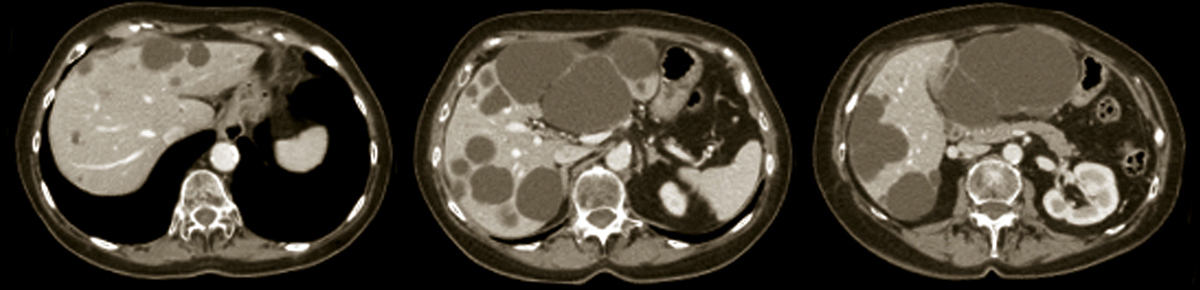

Polykystose hépatique

2. Polykystose hépatique